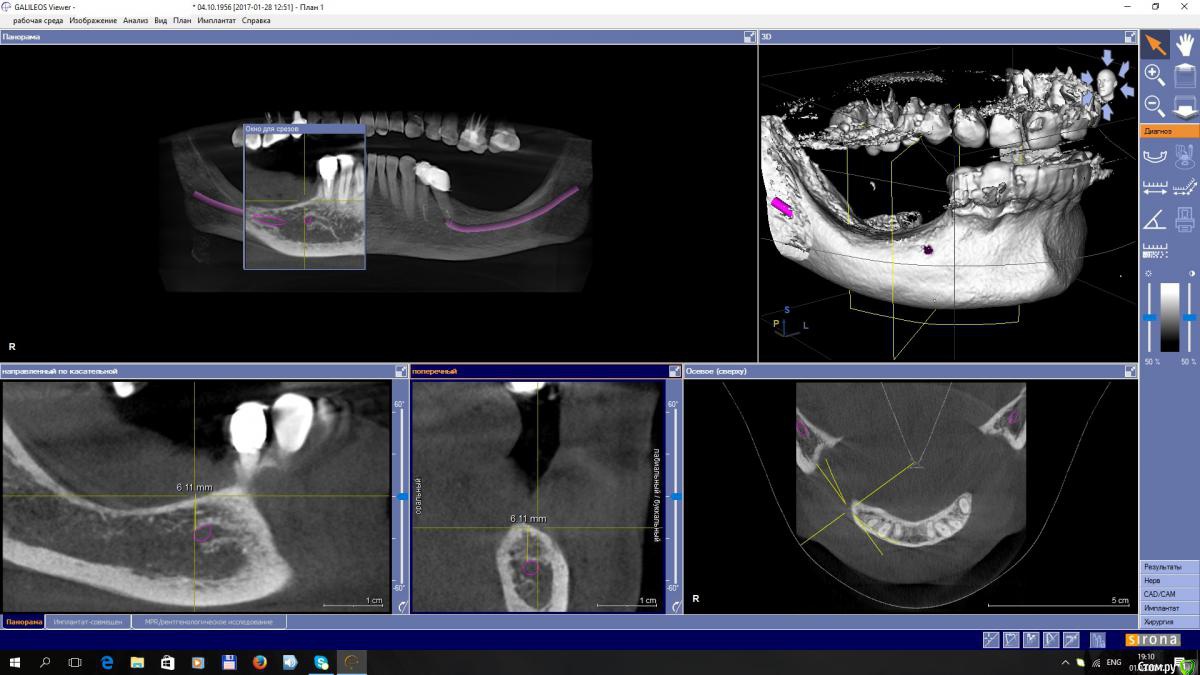

EEcho Опубликовано 3 февраля, 2017 Поделиться Опубликовано 3 февраля, 2017 Уважаемые коллеги! Я в раздумье.Максимально, кость я могу поднять на 4-5 мм, с одной и с другой стороны. Дальше не позволяет межальвеолярная высота.Делать репозицию нерва или все таки пластику с последующей постановкой коротких имплантов. Ссылка на комментарий

Доктор Добрых Дел Опубликовано 3 февраля, 2017 Поделиться Опубликовано 3 февраля, 2017 Но мне кажется латерализация не для данного случая. Я думаю что здесь нужно аугментировать как положено и ставить имплантаты. Верхние зубы спилить и покрыть коронками. 1 Ссылка на комментарий

Dman Опубликовано 13 февраля, 2017 Поделиться Опубликовано 13 февраля, 2017 Дальше не позволяет межальвеолярная высота. почему не позволяет? попросите ортопеда, пусть спилит/покроет коронками выдвинувшиеся антагонисты Ссылка на комментарий